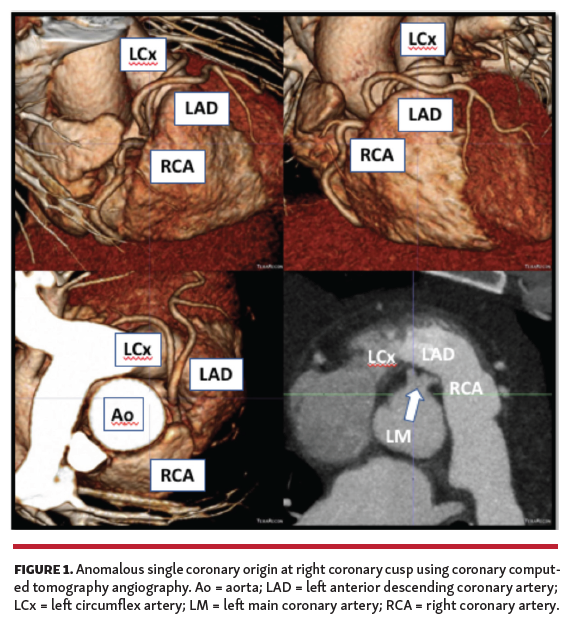

The decision was made to proceed with coronary angiography, which demonstrated anomalous coronary circulation with 1 ostium for all arteries at the site of the right coronary cusp. Vessels were normal caliber and without evidence of disease. The left anterior descending/left circumflex coronary course was not clearly identified and coronary computed tomography angiography (CCTA) was recommended.

CCTA confirmed anomalous common origin anterior to the sinus of Valsalva and the course was prepulmonic (Figure 1). Given the benign prognosis associated with prepulmonic course, the patient was managed conservatively.

Ischemic work-up is important in this group of patients, with coronary angiography being the gold standard. As demonstrated here, CCTA is an essential tool to define artery course and provide further risk stratification. SCAs were originally classified by Lipton et al based on the site of origin and subtypes of anatomical distribution. Some subtypes are higher risk for SCA, especially during exercise due to the artery coursing between the aorta and pulmonary artery. Prepulmonic course is generally associated with a benign course.